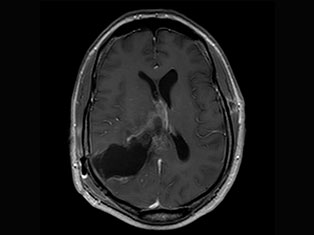

Brain Tumors

A brain tumor is a mass or growth of abnormal cells in your brain. Many different types of brain tumors exist. Some brain tumors are noncancerous (benign), and some brain tumors are cancerous (malignant).